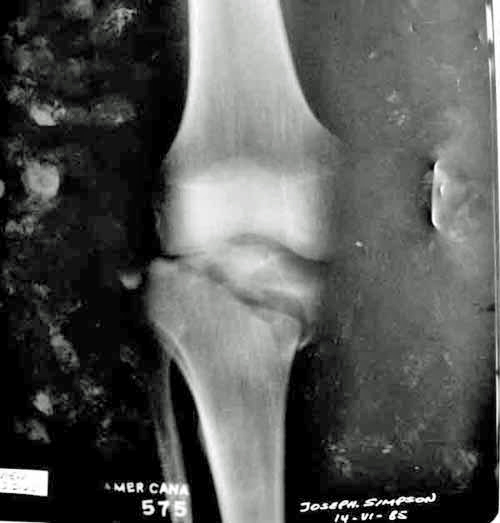

Tibial Plateau Fracture.